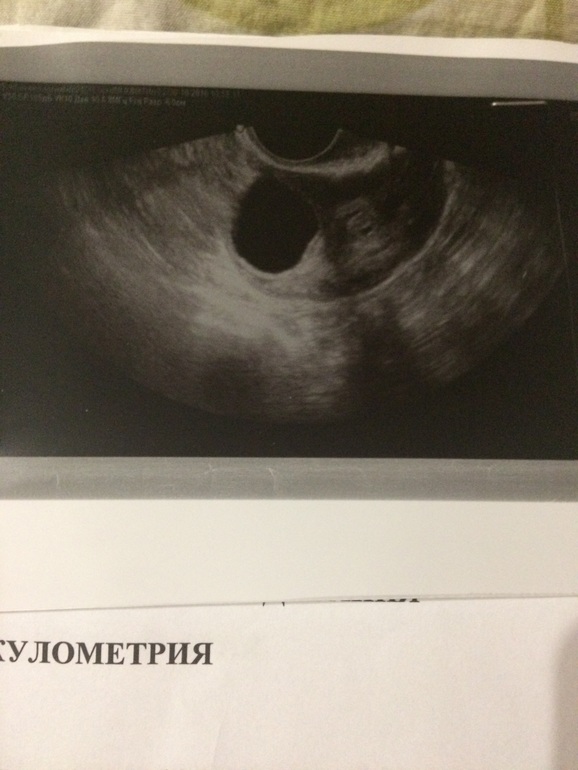

Когда я задала вопрос такой же своему гинекологу, как отличить ЖТ от ДФ, она говорит это сразу видно, также у ЖТ есть признак, это кровоток вокруг (если правильно назвала), типа как на фото

14 дц, ДФ в правом яичнике 24*19 мм 15 дц, ЖТ 14*10мм

13 дц, проовулировавший фолликул 11мм